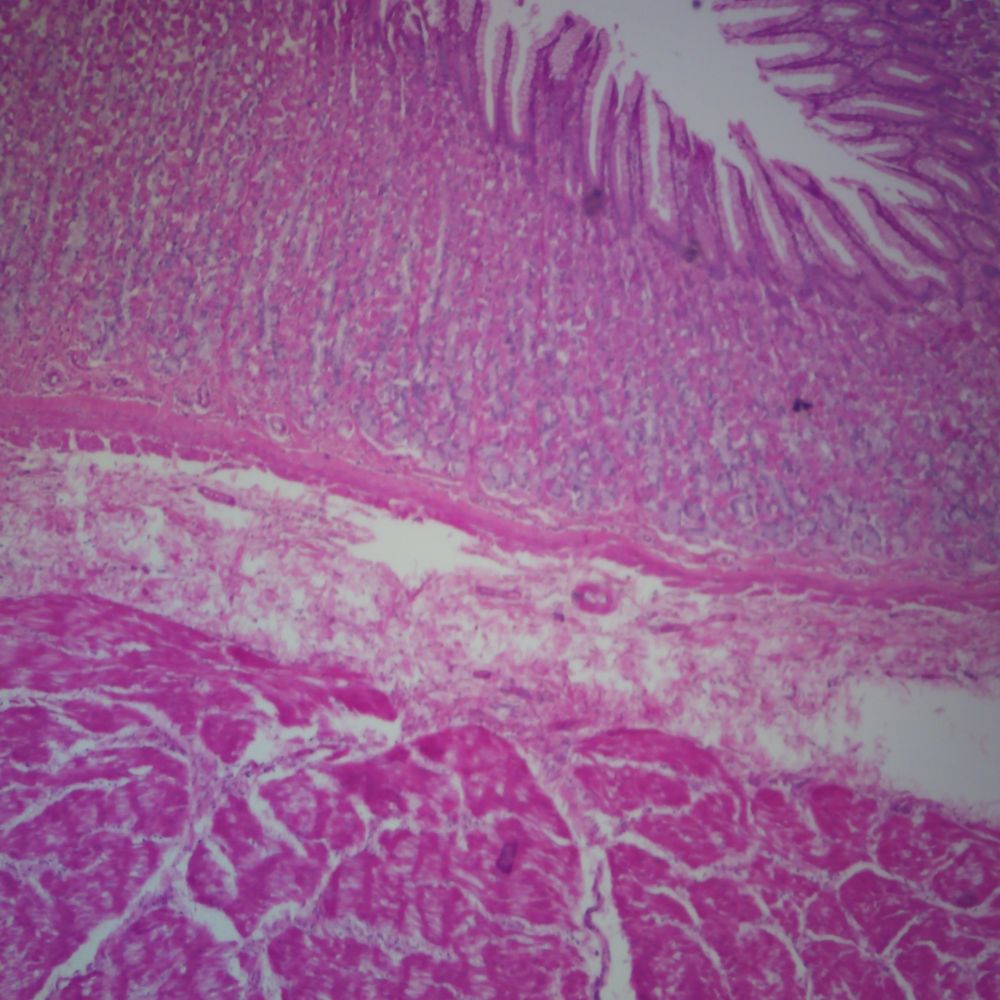

Human stomach slide, section

Esophagus Stomach Junction Histology Labeled Stomach Microscope Slide Labeled Begin by identifying the folds of the. Use the image slider below to learn more about the structure and characteristics of the stomach. Learn the histology of the. — what is the gastric mucosa and which are the most important cells of the stomach? The oesophagus forms a junction with the. this slide shows the structure of the. Stomach Microscope Slide Labeled.